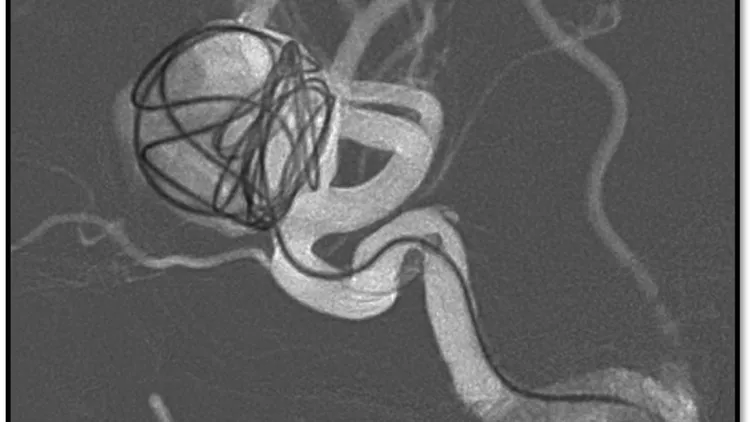

阮郁修採用「血流導向裝置輔助線圈栓塞術」,使用特殊導管經由鼠蹊部穿刺進去,將導管放置於內頸動脈,並透過導管將纏繞的線圈放進動脈瘤的空腔,以及將血流導向裝置放置於動脈瘤開口,讓動脈瘤內的血流停滯產生栓塞,重新把血流引導到正常的血管,使動脈瘤體積逐漸縮小不再復發。統計顯示此類手術成功率達9成以上,而術後半年8成的動脈瘤就會栓塞,術後3年98%的動脈瘤完整栓塞。